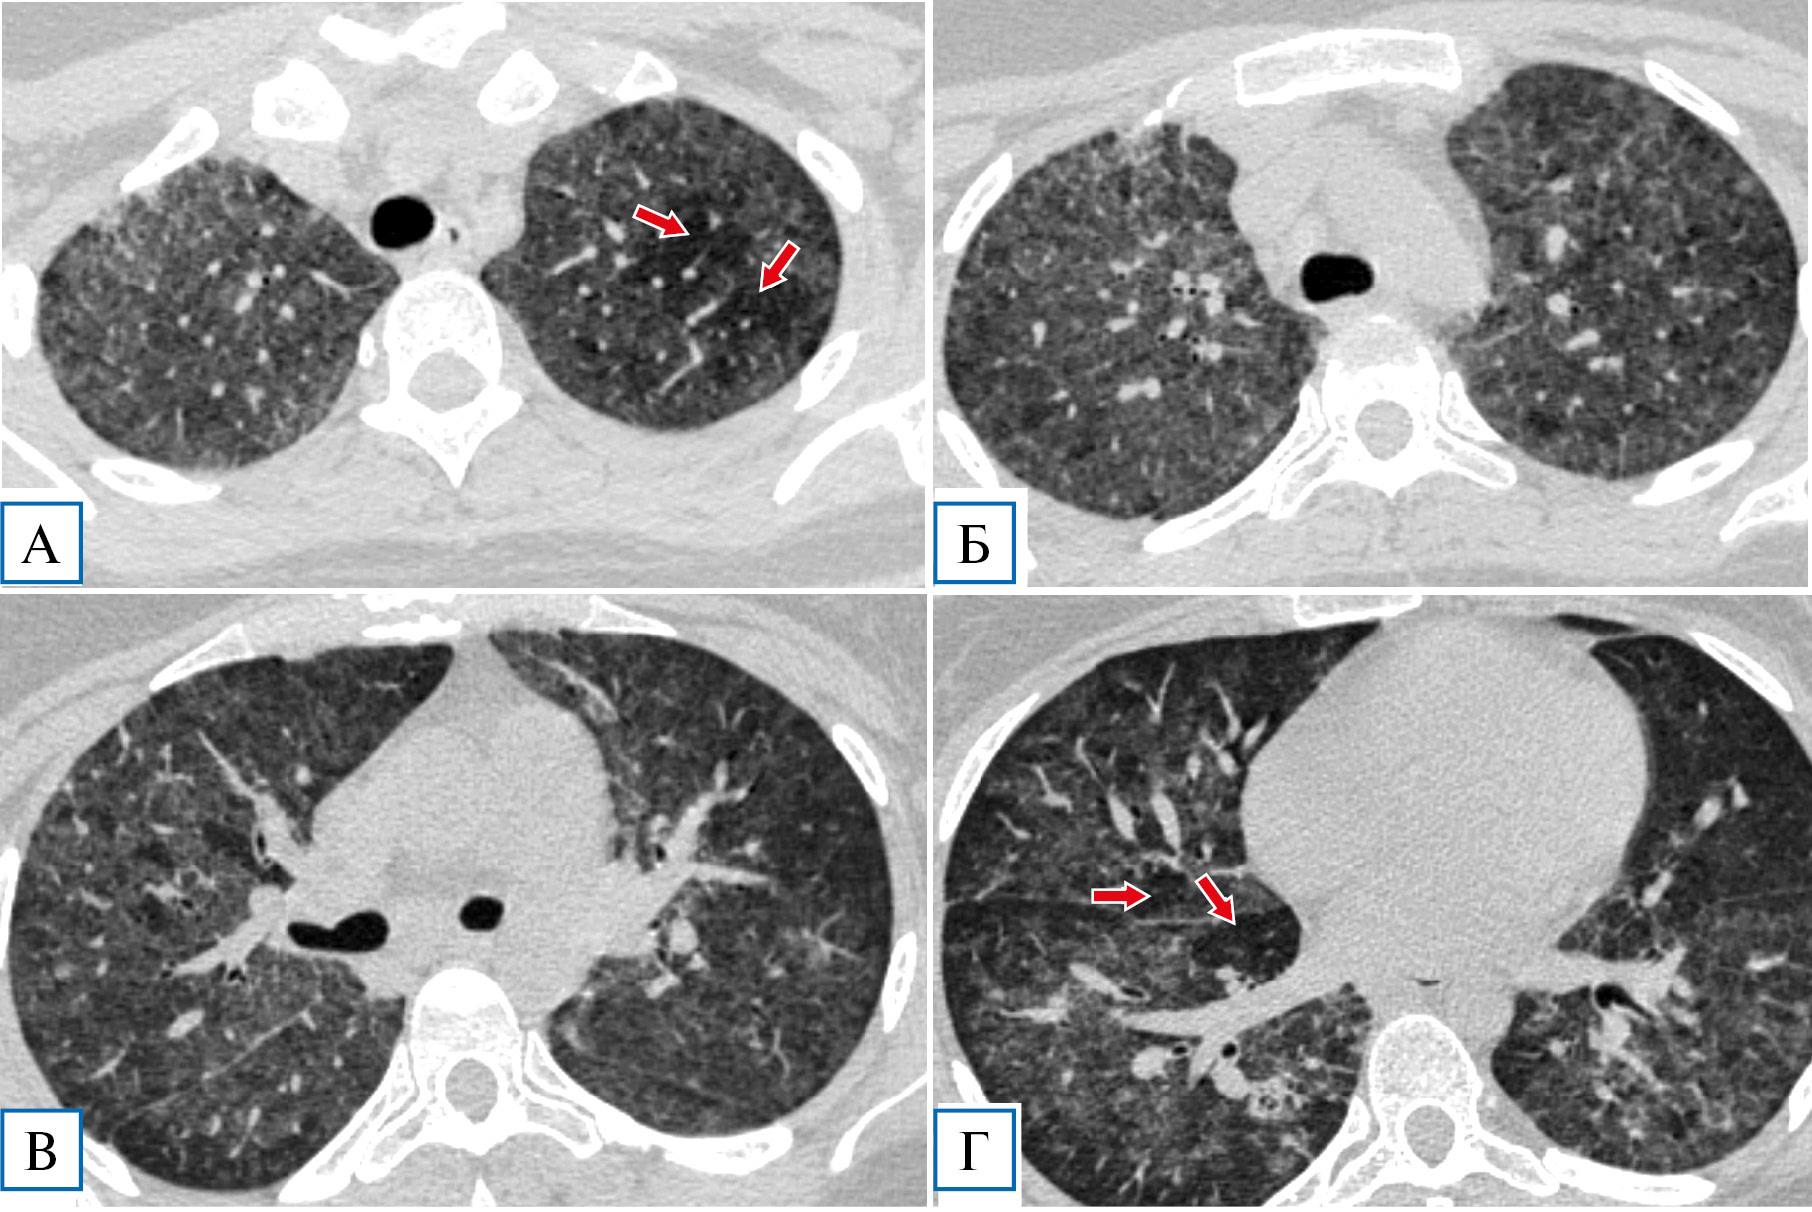

Диагноз коронавирусной инфекции изменен на диагноз пневмоцистной пневмонии на фоне ВИЧ-инфекции, в связи с чем начата терапия ко-тримоксазолом (в дозе 1920 мг внутривенно капельно 4 раза в день), глюкокортикостероидами (метилпреднизолон по 250 мг внутривенно капельно в первые трое суток, далее перорально по 16–12 мг/сут), а также антикоагулянтная, дезинтоксикационная терапия. В течение первых 12 ч от начала терапии отмечалась дальнейшая положительная клиническая динамика в виде полной нормализации температуры тела, регресса дыхательной недостаточности (сатурация О2 на атмосферном воздухе составляла 97%), уменьшения кашля и астении. В дальнейшем отмечено улучшение лабораторных показателей: нормализация уровней лейкоцитов, С-реактивного белка (3,1 мг/л), ИЛ6, прокальцитонина, снижение лимфопении до 7,5% (0,67 в абсолютных значениях). Также была обнаружена положительная КТ-динамика в виде значительного регресса зон «матового стекла» (рис. 2). Пациентка была выписана с рекомендациями продолжения терапии ко-тримоксазолом и метилпреднизолоном перорально еще не менее 2 нед и обращения в СПИД-центр для дальнейшего обследования и назначения антиретровирусной терапии.

Рис. 2. Пациентка Я., 29 лет: контрольная компьютерная томография грудной клетки на 7-й день госпитализации

Примечание. Отмечается существенная положительная динамика: сохраняются отдельные фокусы «матового стекла» преимущественно в верхних долях (А, Б, показаны стрелками), в нижних долях минимальные интерстициальные изменения (В, Г). «Воздушные ловушки» не визуализируются.